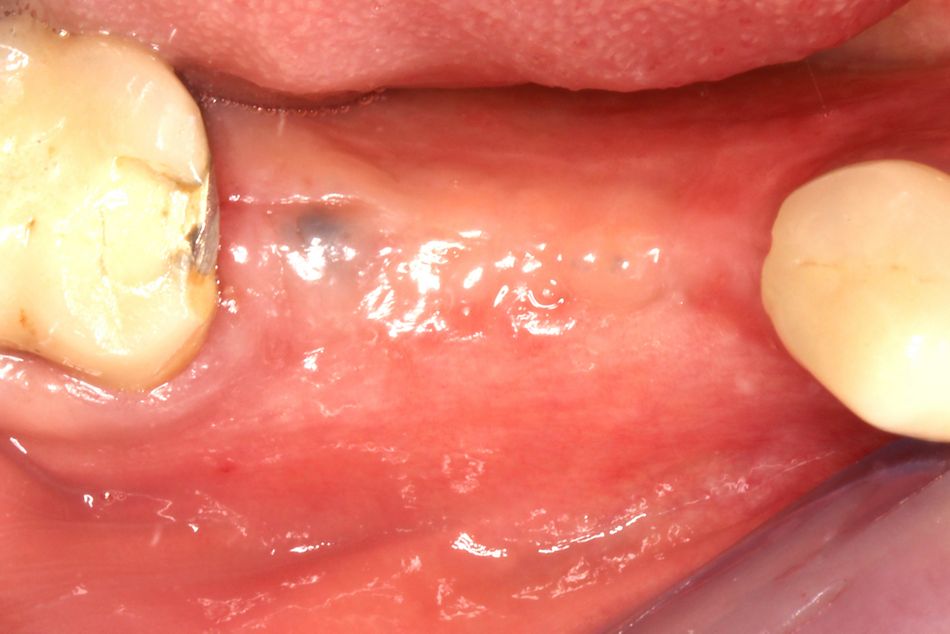

Following 5 months of uneventful healing, the patient presented for the next procedure, which included the insertion of two fixed dental implants and simultaneous soft tissue thickening (Fig. 13). The previously placed incision lines were reopened in order to remove the titanium osteosynthesis screws used for cortical strut fixation (Fig. 14). Vital, bleeding and robust bone was found within the granule-filled space adjacent to the avital cortical strut, which was flush-mounted in the new formed bone tissue (Fig. 15). Horizontal bone gain was sufficient for stable and fully submerged implantation of the designated Straumann BLT implants with a torque value of 35 Ncm (Figs. 16-17). Subsequently, cover screws were inserted in the implants, and bone substance, which was being removed during placement of the pilot drill, was used for contouring around the implant shoulders (Fig. 18). Prior to wound closure, which was performed with double-sling sutures, a porcine collagen matrix (botiss mucoderm®) was placed over the augmentation site to thicken the soft tissue (Figs. 19-20). A radiographic control image was recorded in order to assess implant position and bone density within the augmented area (Fig. 21).

Following 3 months of healing, the thickened soft tissue presented a natural and healthy appearance, so that papilla shaping could be achieved by the installation of gingival formers to set the course for a positive aesthetic final outcome (Figs. 22-23). Well-conditioned soft tissue was found 5 weeks later when the gingiva formers were removed and the final prosthetic restoration was installed (Fig. 24).